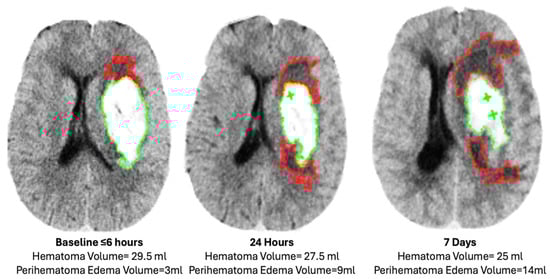

| Imaging Parameters Median (IQR) | At Baseline | At 24 H | At 7 Days | ||||||

|---|---|---|---|---|---|---|---|---|---|

| Intervention (n = 31) | Control (n = 29) | p | Intervention (n = 27) | Control (n = 23) | p | Intervention (n = 16) | Control (n = 21) | p | |

| IPH vol. (mL) | 14 (7–27) | 10 (6–15) | 0.1 | 15 (8–29) | 10 (7–18) | 0.1 | 12 (8–18) | 12 (8–18) | 0.3 |

| IVH vol. (mL) | 0 (0–7) | 0 (0–9) | 0.6 | 0 (0–8) | 0 (0–7) | 0.9 | 0 (0–1) | 0.5 (0–4) | 0.3 |

| TH vol. (mL) | 21 (8–30) | 13 (8–28) | 0.2 | 20 (10–37) | 17 (9–26) | 0.1 | 14 (8–18) | 14 (11–24) | 0.5 |

| Absolute PHE vol. (mL) | 14 (7–26) | 10 (3–21) | 0.3 | 22 (10–41) | 14 (9–26) | 0.1 | 33 (10–46) | 29 (20–38) | 0.3 |

| Relative PHE vol. (mL) | 0.75 (0.52–0.95) | 0.91 (0.54–1.24) | 0.3 | 1.20 (0.92–1.44) | 1.33 (0.82–1.67) | 0.7 | 1.99 (1.29–2.67) | 1.95 (1.44–3.06) | 0.6 |

| EED (cm) | 0.58 (0.34–0.79) | 0.51 (0.29–0.79) | 0.8 | 0.77 (0.52–0.95) | 0.64 (0.51–0.84) | 0.3 | 1.10 (0.59–1.17) | 1.03 (0.89–1.19) | 0.7 |